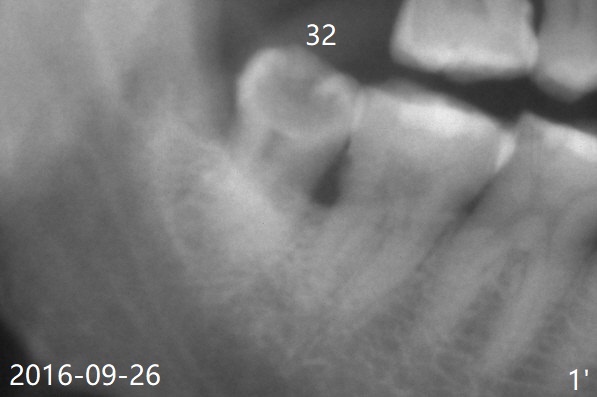

rhPDGF-BB     Last     Next

Xin Wei, DDS, PhD, MS 1st edition 03/12/2020, last revision 03/31/2020